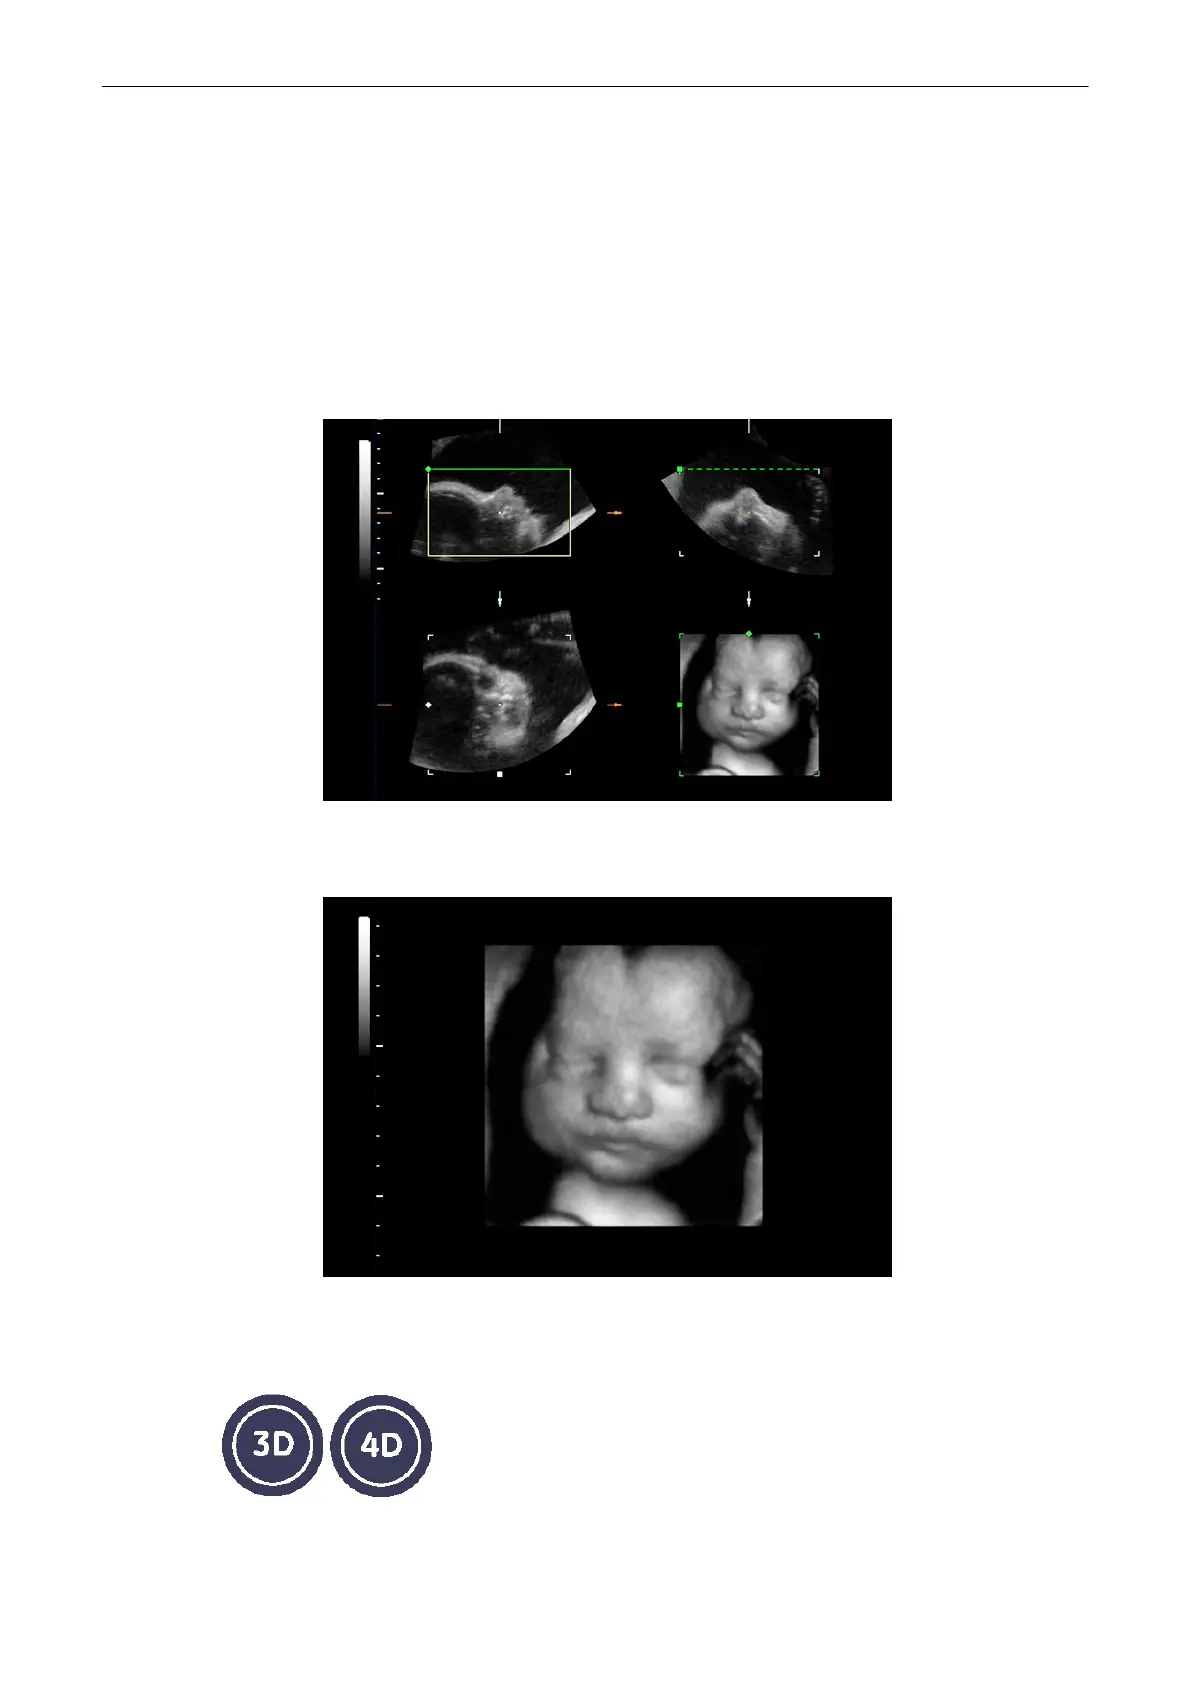

The Volume mode allows for scanning a tissue volume and subsequent analysis of sections of

the volume in 3 dimensions. The liberal selection of sections within the volume and the

simultaneous real-time 4D display of three orthogonal planes and a rendered 3D image

represents a new dimension for e.g., the diagnosis of fetal abnormalities. The Volume mode

provides access to sections unachievable by the 2D scan technique. A parallel interface

provides the possibility to save volume data on a hard disk drive for repeated analysis

anytime.

Example of fetal “facing” in multiplanar sections and surface rendering.

The volume data sets may be processed by means of the software option “interactive volume

rendering” and “Real Time 4D” for surface or transparent mode images.